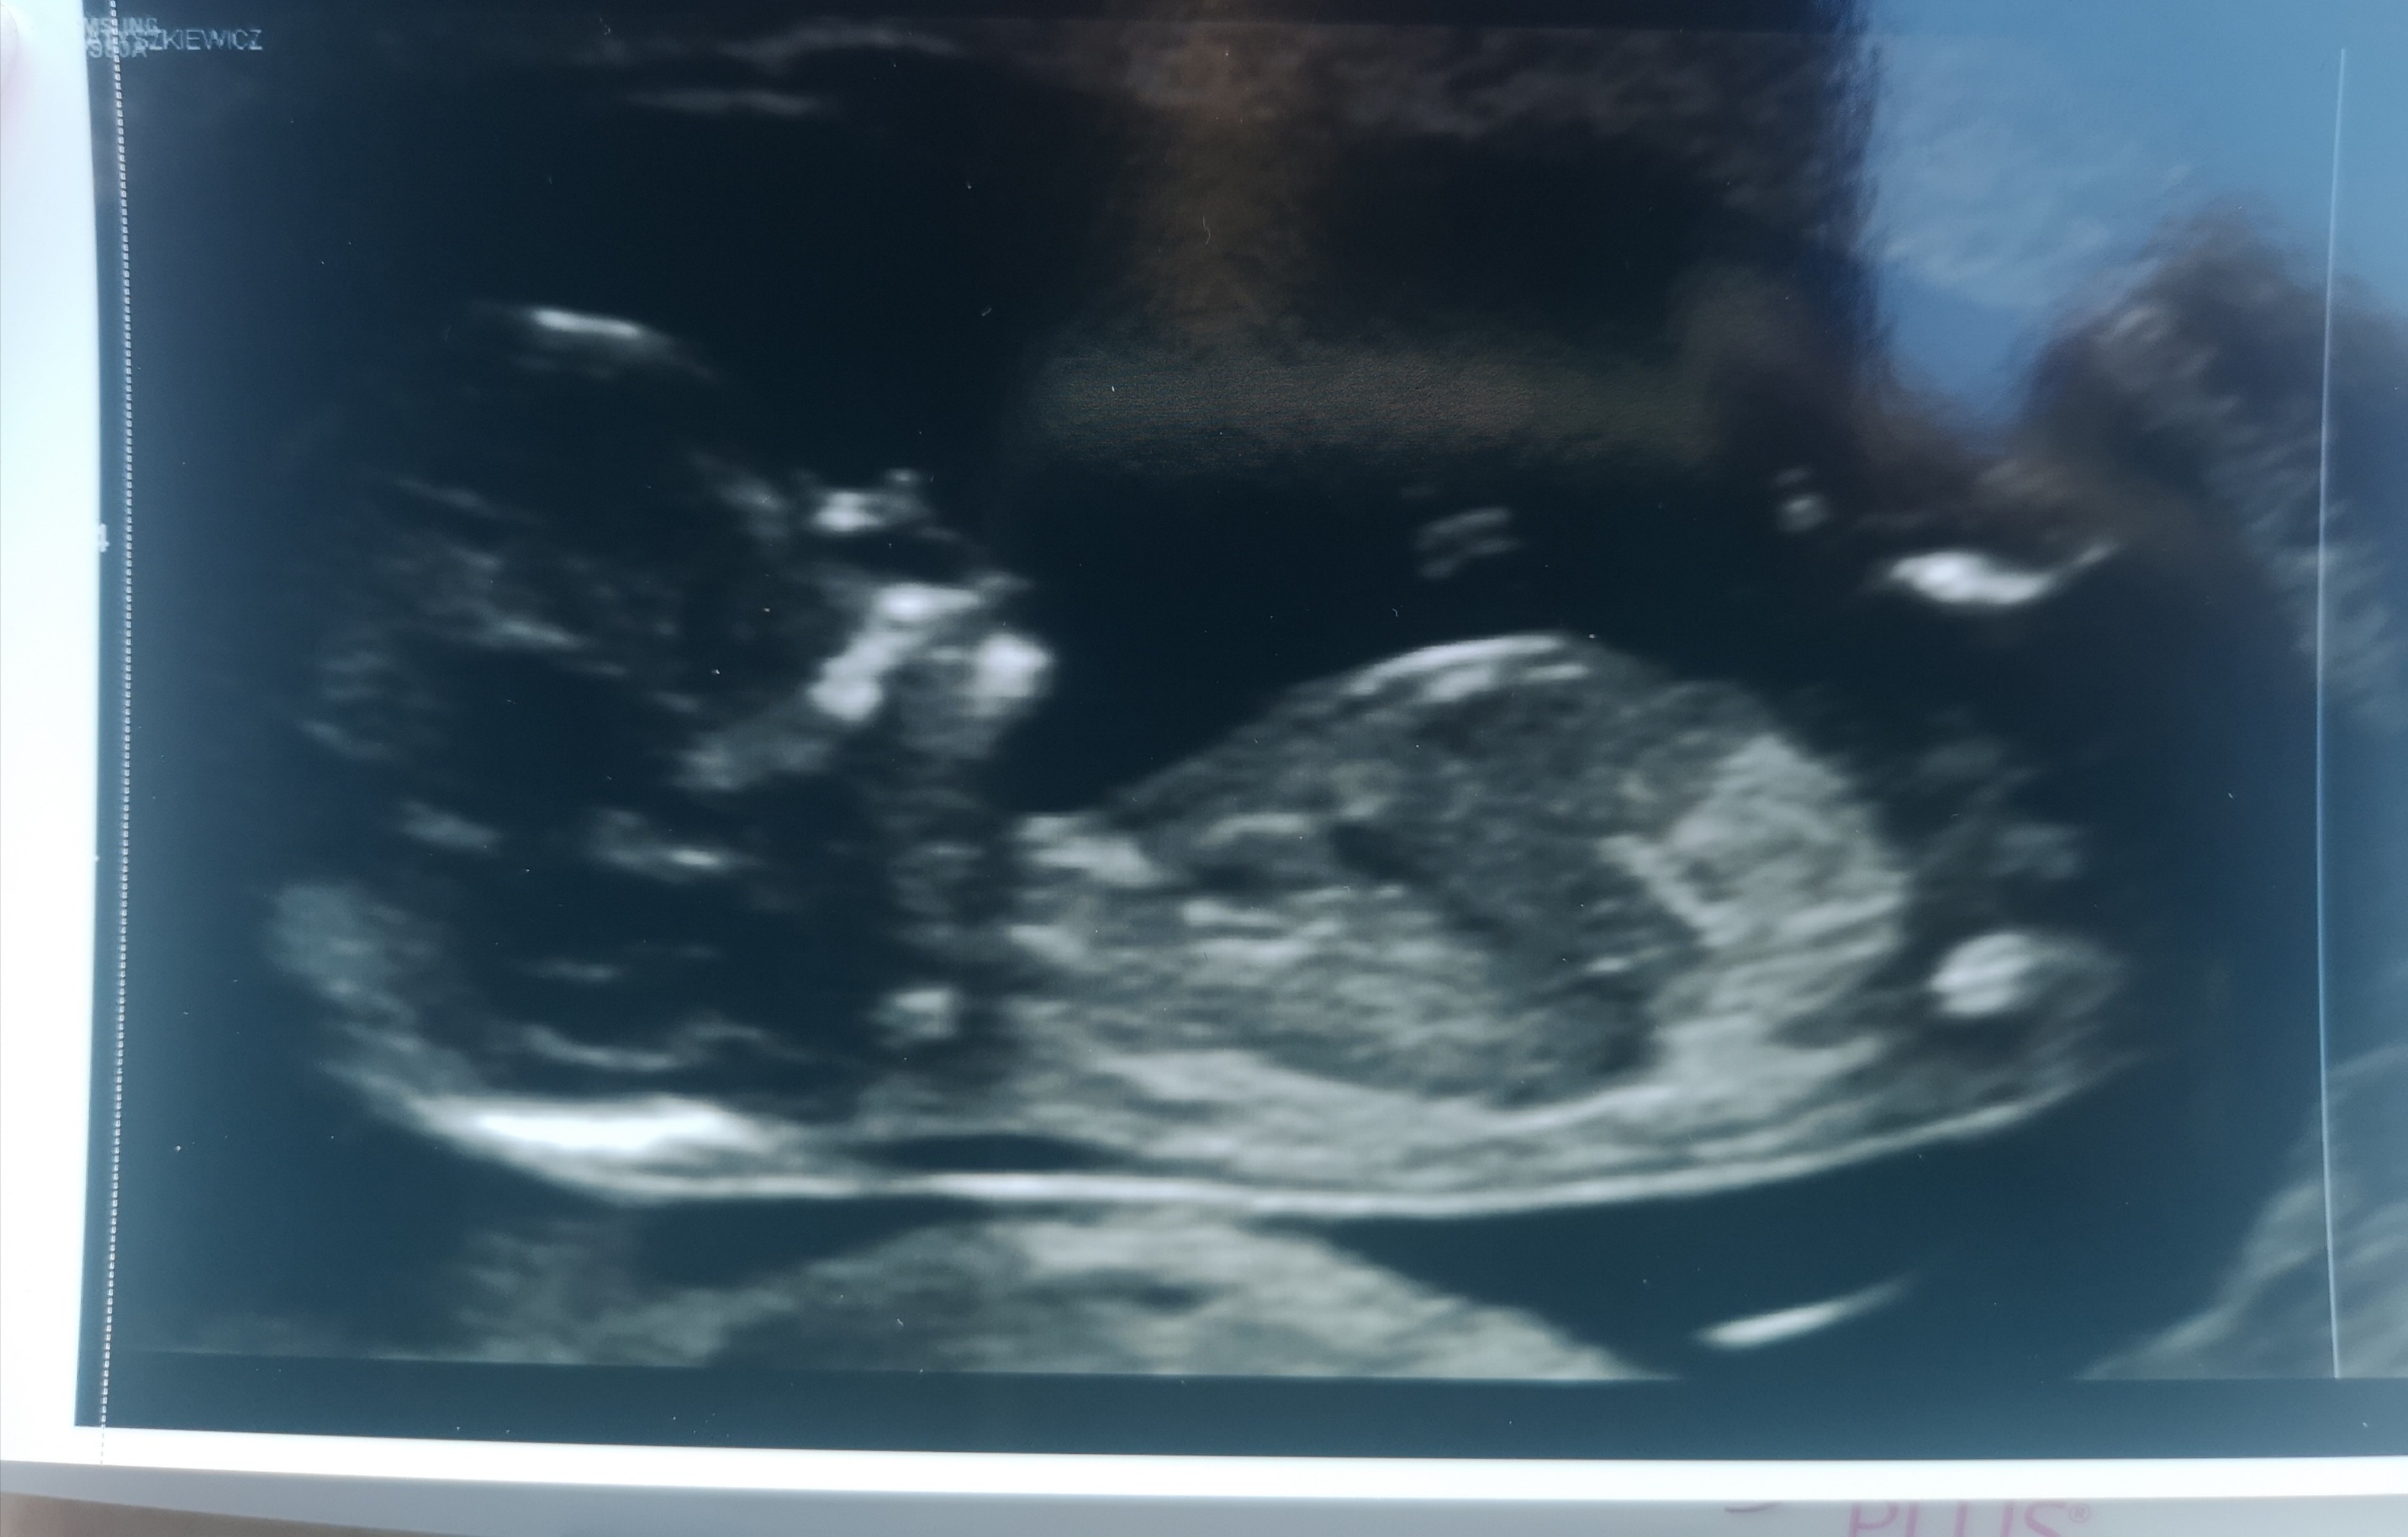

Ja już tak wgl po prenatalnych, wszystko książkowo, pani wszystko wytłumaczyła i mierzyła dokładnie, powiedziała że nie widzi potrzeby robienia pappa a byłam przekonana że zrobię, ponieważ powiedziała że po usg widzi że jest wszystko pięknie że aż miło. Więc jej zaufałam, nawet te triso mię wyszły ponad statystykę, mam nadzieję że dobrze zrobiłam. Poznałam też płeć i jestem taaaaaaka szczęśliwa bo chciałam bardzo dziewczynkę mimo że czułam że bedxie chłopiec byłam przekonana, bo u mnie zawsze na opak wychodzi. A tu piękna niespodzianka. Troszkę mbie na badaniu wytarmosiła bo mówi że jestem bardzo szczupła (hellow w końcu schudłam 20 kg żeby zajść wgl w ciążę) i w dodatku mała się nam chowała. Ale udało się pieknoe wszysyko zmierzyć. Idę dziś, mimo tej bakterii, która wczoraj wyjęła mi kilka godzin na łzy z życia, spokojnie spać :)

Cudowne wiesci i zdjecie. Relaksuj się ile wlezie 😁🥰